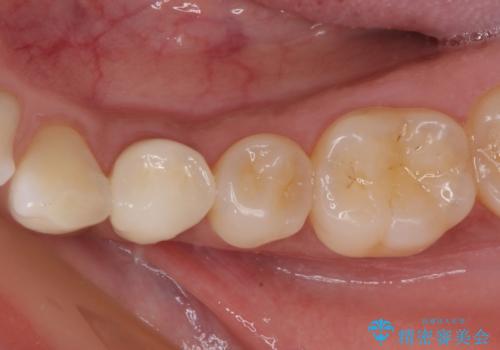

目立つ銀歯と欠けてしまった詰め物 オールセラミッククラウンでの補綴治療

不快感の強い奥歯 オールセラミッククラウンでのむし歯治療